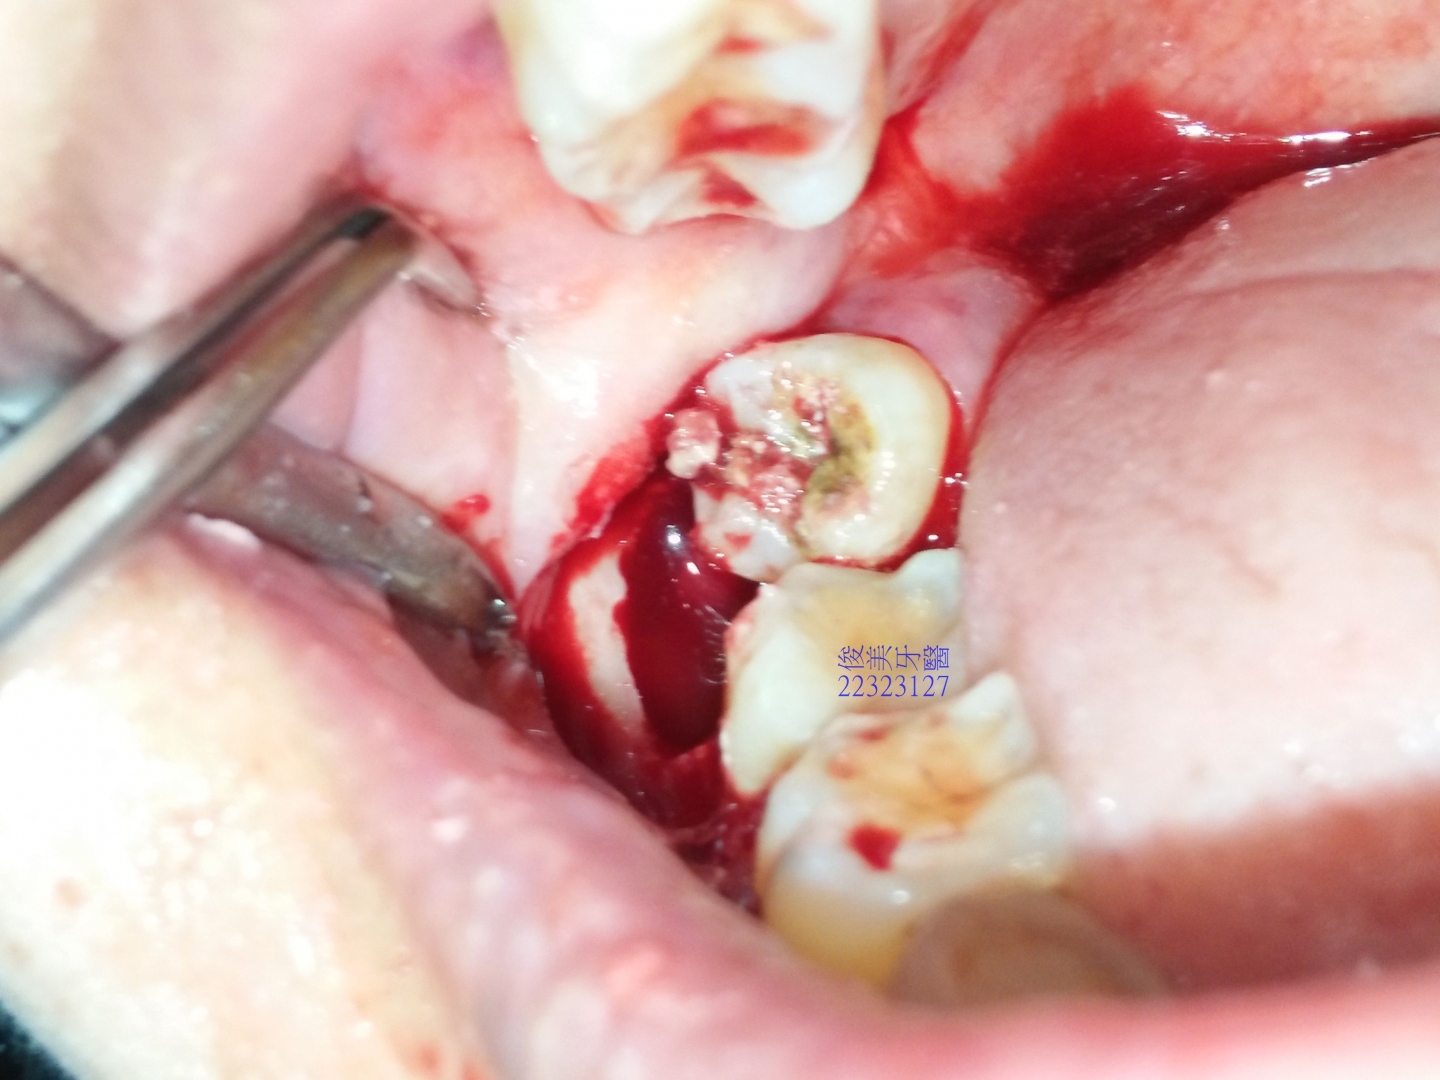

全部取出,止血後縫合,患者需強力冰敷3天,以免腫太大及脹痛,一週後回診拆線即可。

觀察傷口狀況 。